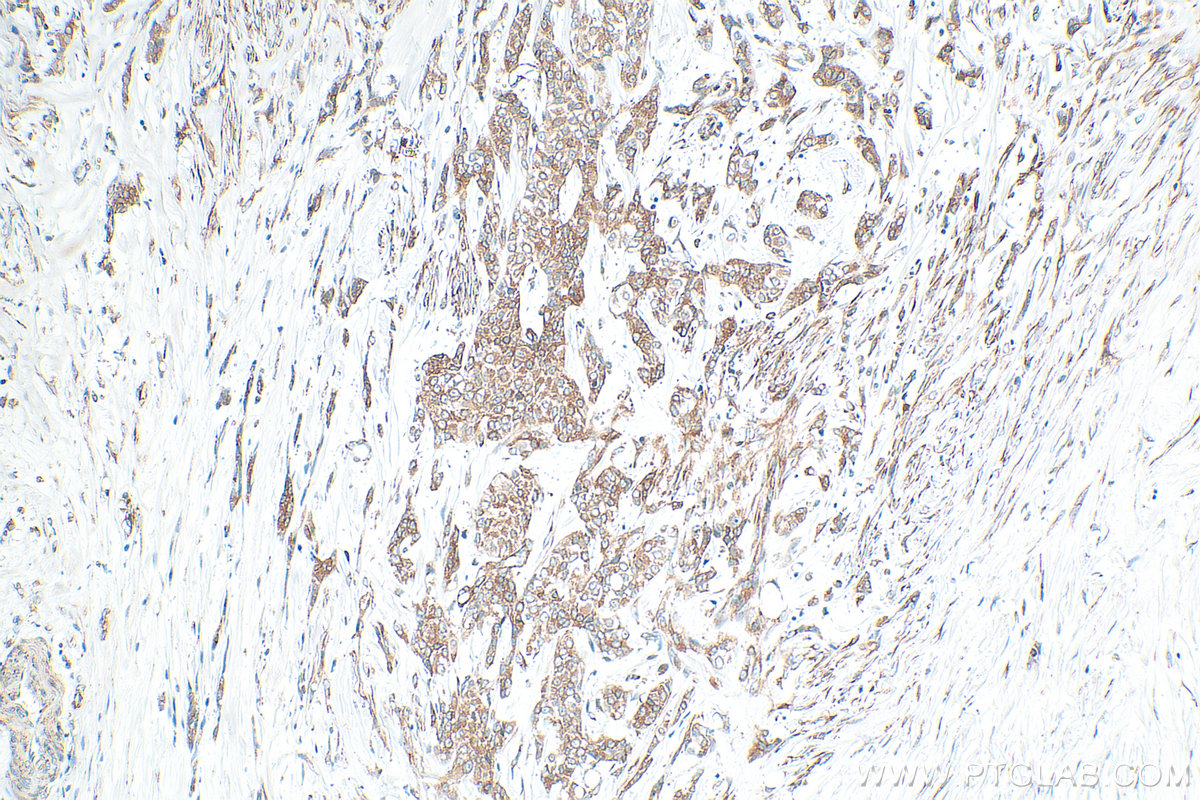

| Positive IHC detected in | human intrahepatic cholangiocarcinoma tissue, human urothelial carcinoma tissue Note: suggested antigen retrieval with TE buffer pH 9.0; (*) Alternatively, antigen retrieval may be performed with citrate buffer pH 6.0 |

| Immunohistochemistry (IHC) | IHC : 1:200-1:800 |